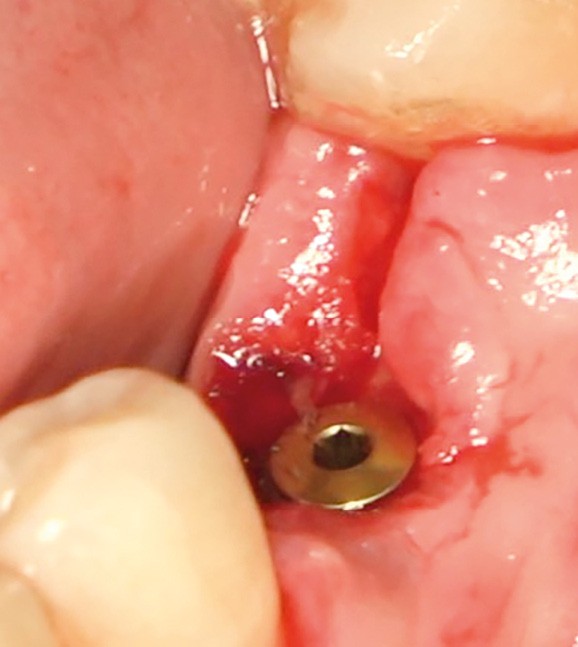

- Avulsion de la 36 et régénération osseuse guidée (ROG) réalisée en 2017 suite à une fracture de la dent et une infection

- Un implant posé en 2018 après la fin du traitement orthodontique

- Péri-implantite diagnostiquée en 2021

Chez ce patient, le traitement de la péri-implantite a comporté une chirurgie associant décontamination électrolytique de la surface implantaire, régénération osseuse guidée et enfouissement de l’implant. Le résultat à 2 ans est très moyen au vu du pourcentage de régénération osseuse obtenu. Comment peut-on prévoir un tel résultat alors que l’on a suivi les recommandations à la lettre, que l’on a utilisé les dernières technologies de décontamination, que l’on y a mis tous les moyens, que le patient est en bonne santé générale et qu’il vient en plus régulièrement aux séances de thérapeutique de soutien ? Le succès du traitement des péri-implantites n’est pas simple à obtenir, surtout quand un élément clé est compromis… la maintenance personnelle ! En effet le succès n’est possible que si le contrôle de plaque quotidien est optimal et, ici, ça n’était pas le cas. Le patient se brossait certes les dents, mais ne passait pas quotidiennement les brossettes, ce qui…